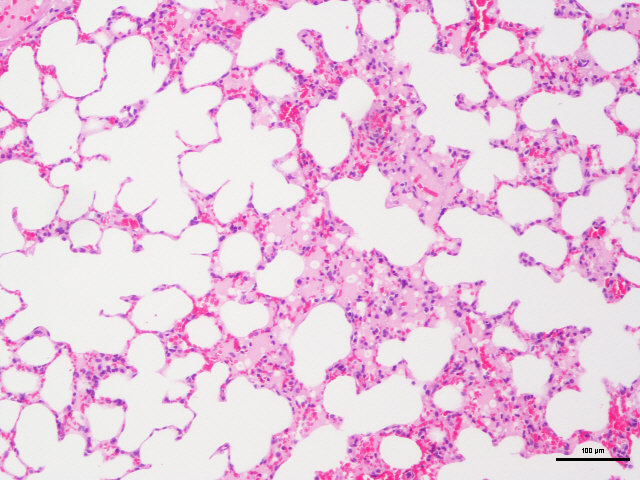

样片参考:

肺